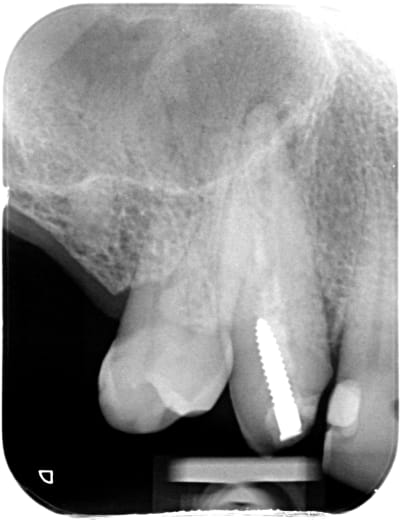

X ray 03 medium zvq18j - Eugenol